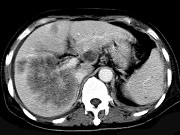

男,42岁,中上腹痛,轻度黄疸,结合CT图像,提出最可能的诊断 ( ) XH-26761.jpg XH-26762.jpg XH-26763.jpg

题型: 单选题 分类: 肿瘤放射治疗学

• A.肝脓肿

• B.肝多发性囊肿

• C.肝癌肝内转移伴门脉癌栓形成

• D.胆管细胞癌

• E.肝血管瘤